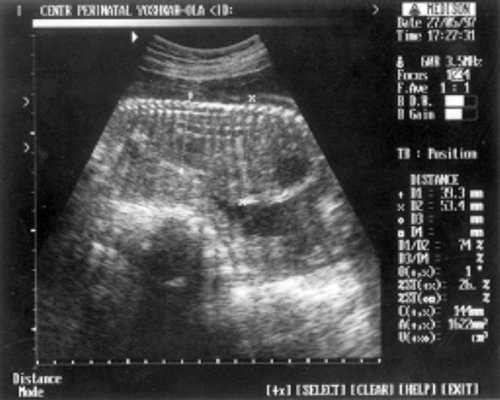

- Плечевая кость = 16 мм - 14,5 нед. (рис. 3)

Рис. 3. УЗИ плода - плечевая кость.